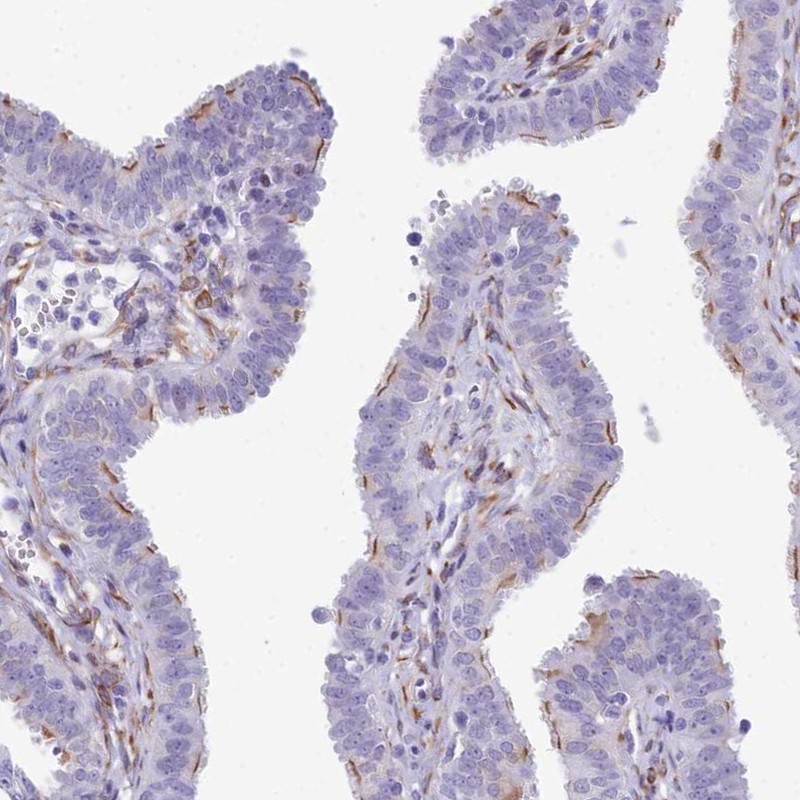

Immunohistochemical staining of human fallopian tube shows strong positivity in ciliated cells.